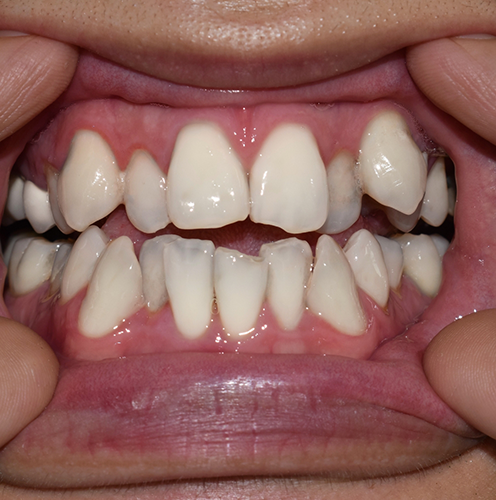

Do I Need a Tooth Extraction?

Dr. Sarcos will always thoroughly evaluate the affected tooth, the nearby teeth and gums, as well as your overall health, before determining if tooth extraction is the best course of action.

That said, the most common reasons a tooth may need to be removed include:

- Severe decay has destroyed too much of the existing tooth’s structure

- Advanced periodontal disease has compromised the bone tissue supporting the tooth

- There is a painful infection that cannot be resolved with a root canal

- Significant overcrowding is preventing the other teeth from erupting properly

- Trauma or a fracture below the gumline has made the tooth unsalvageable

- A tooth or teeth need to be removed before orthodontic treatment or the placement of a denture/dental implants